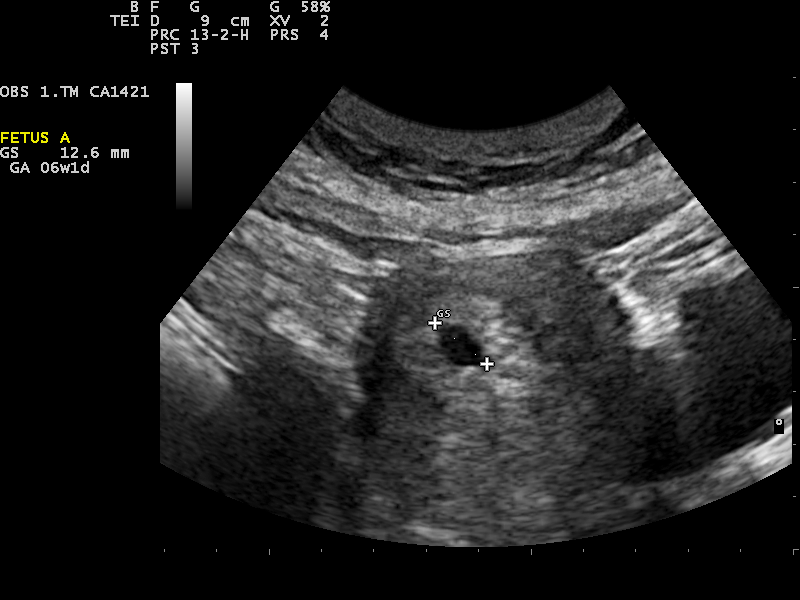

Estimados, por favor me gustaría saber si tengo posibilidades de embarazo, el día 15 de Enero me hicieron una transferencia de 1 embrión de 5 días post congelado (ICSI), el día 25 (a 10 días)me hice la beta y salió 32,5, mi doc dijo que era demasiado baja, la repetí a las 48 hrs y salió 54,4, luego me la repetí a las 48 hrs y salió 137,6 y me la hicieron repetir 4 días después y salió 557,7, me dice que sigue siendo baja al día 18 post transfer pero que igual duplica, me gustaría saber si hay posibilidades de que el embarazo sea viable. muchas gracias! tengo mucha fe!

Los valores iniciales de la B-HCG son variables y no siempre nos pronostican la evolución del embarazo. En estos casos lo ideal es realizar una monitorización de la evolución de la hormona para poder predecir cual es la situación del embarazo. Lo normal es que los valores de la hormona se dupliquen cada 48h pero antes de establecer un diagnóstico se debe de valorar la situación con el médico responsable.